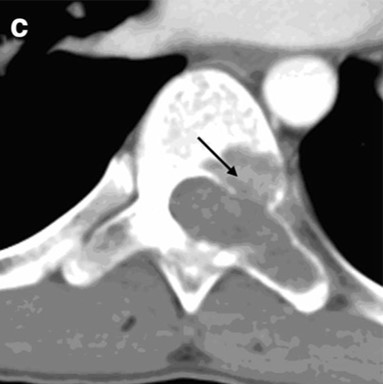

• CT

• 左:CT(骨条件)、右:造影CT